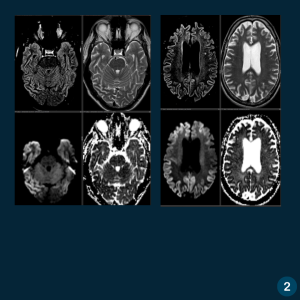

Caso do Dia – Encefalopatia espongiforme